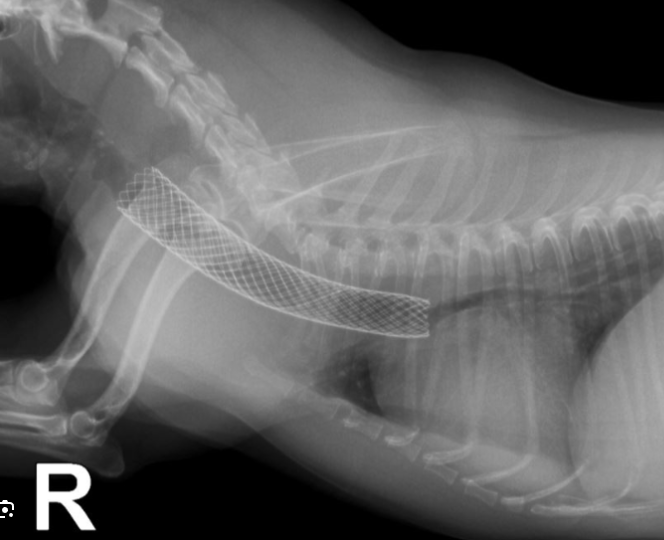

기관 허탈은 소형견에서 흔히 발생하는 만성 호흡기 질환으로, 기관 내 스텐트 시술은 널리 사용되는 치료법 중 하나입니다. 본 연구는 개의 기관 스텐트 시술 후 발생하는 합병증의 유병률을 조사하기 위한 체계적인 문헌 고찰 및 메타 분석 연구입니다. 2000년부터 2020년까지 발표된 문헌을 검색하여 15개의 연구를 분석하였습니다.

결과는 위와 같다. 즉, 기침을 제거하기 위해 하는 시술이 아니라는것이다. 확연한 부작용도 상당하다. 스텐트 골절에 대해서도 본문에서는 비교적 드물다고 표현하고 있지만 12%것은 10 중 1마리는 사망한다는것과 다르지 않아 본문의 표현과는 달리 심각한 문제로 받아들여야 한다.

그러므로 기관 스텐트 시술은 다음과 같은 개에게 권장된다.

다만, 기관 스텐트 시술은 합병증 발생 가능성이 있으므로, 생명을 위협하는 기도 폐쇄나 삶의 질이 현저히 저하된 경우와 같이 꼭 필요한 경우에 한하여 신중하게 고려되어야 한다.